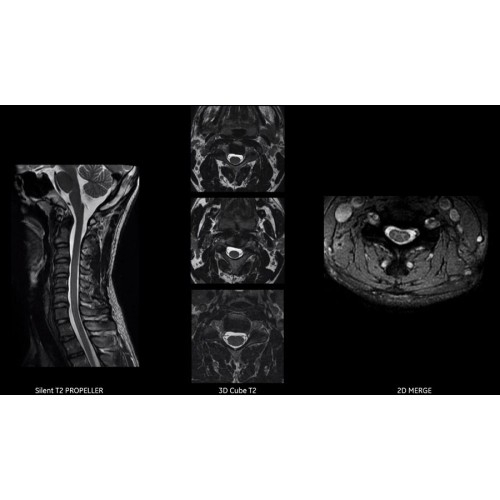

МРТ аппарат GE SIGNA Voyager 1.5T позволяет проводить полный спектр магнитно-резонансных исследований, включая нейровизуализацию, исследования опорно-двигательного аппарата, органов брюшной полости и малого таза, а также специализированные кардиологические программы.

• Ортопедия и травматология